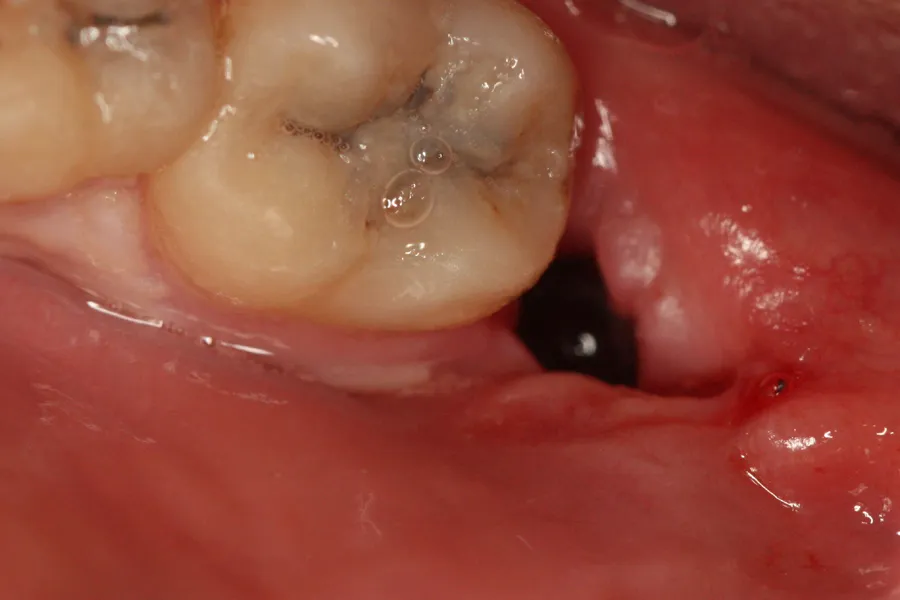

- Obecność stabilnego skrzepu: W zębodole widzisz ciemny, stabilny skrzep, który nie jest ani wypłukany, ani rozpuszczony.

Suchy zębodół, medycznie nazywany zapaleniem zębodołu, występuje, gdy skrzep krwi, który powinien chronić ranę, nie uformuje się prawidłowo lub zostanie usunięty z zębodołu. W efekcie odsłonięta zostaje kość i zakończenia nerwowe, co prowadzi do silnego bólu. Ból ten jest zazwyczaj pulsujący, często promieniujący do ucha, skroni, a nawet szyi. Pojawia się zazwyczaj po 2-5 dniach od zabiegu, kiedy początkowy ból poekstrakcyjny powinien już ustępować. To właśnie jego intensywność i późne pojawienie się są charakterystyczne dla suchego zębodołu.

- Pusty zębodół jeśli zajrzysz do ust i zobaczysz, że w miejscu po zębie nie ma skrzepu, a jest widoczna kość.